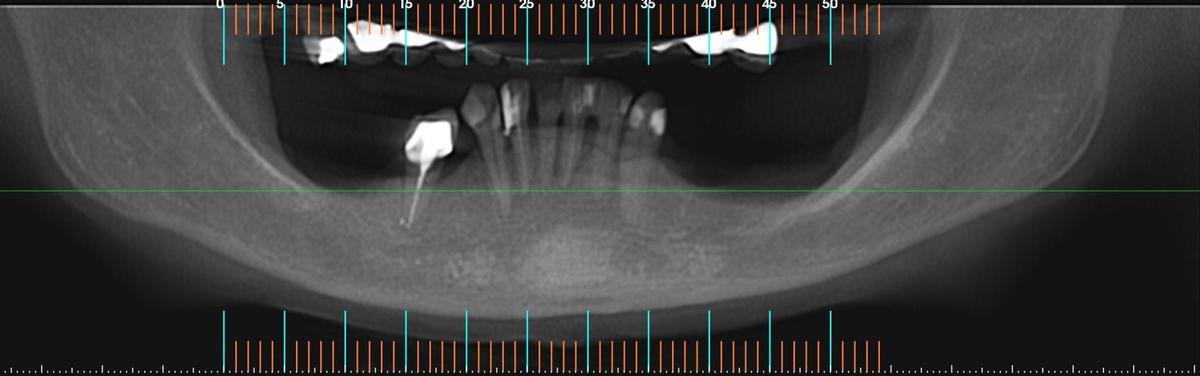

PRÓTESE TOTAL FIXA EM IMPLANTES

M.C.R.B.S.